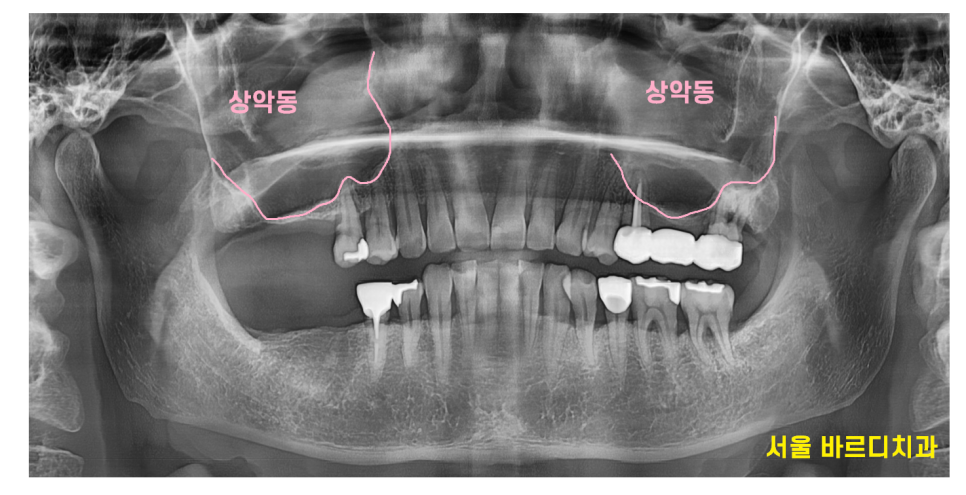

- 상악동이란 무엇인가요?

상악동, 이비인후과에서는 부비동이라고도 하죠!

코 양옆에 위치한 빈 공간으로,

우리가 숨을 쉬거나 소리를 낼 때 중요한 역할을 하고 있습니다.